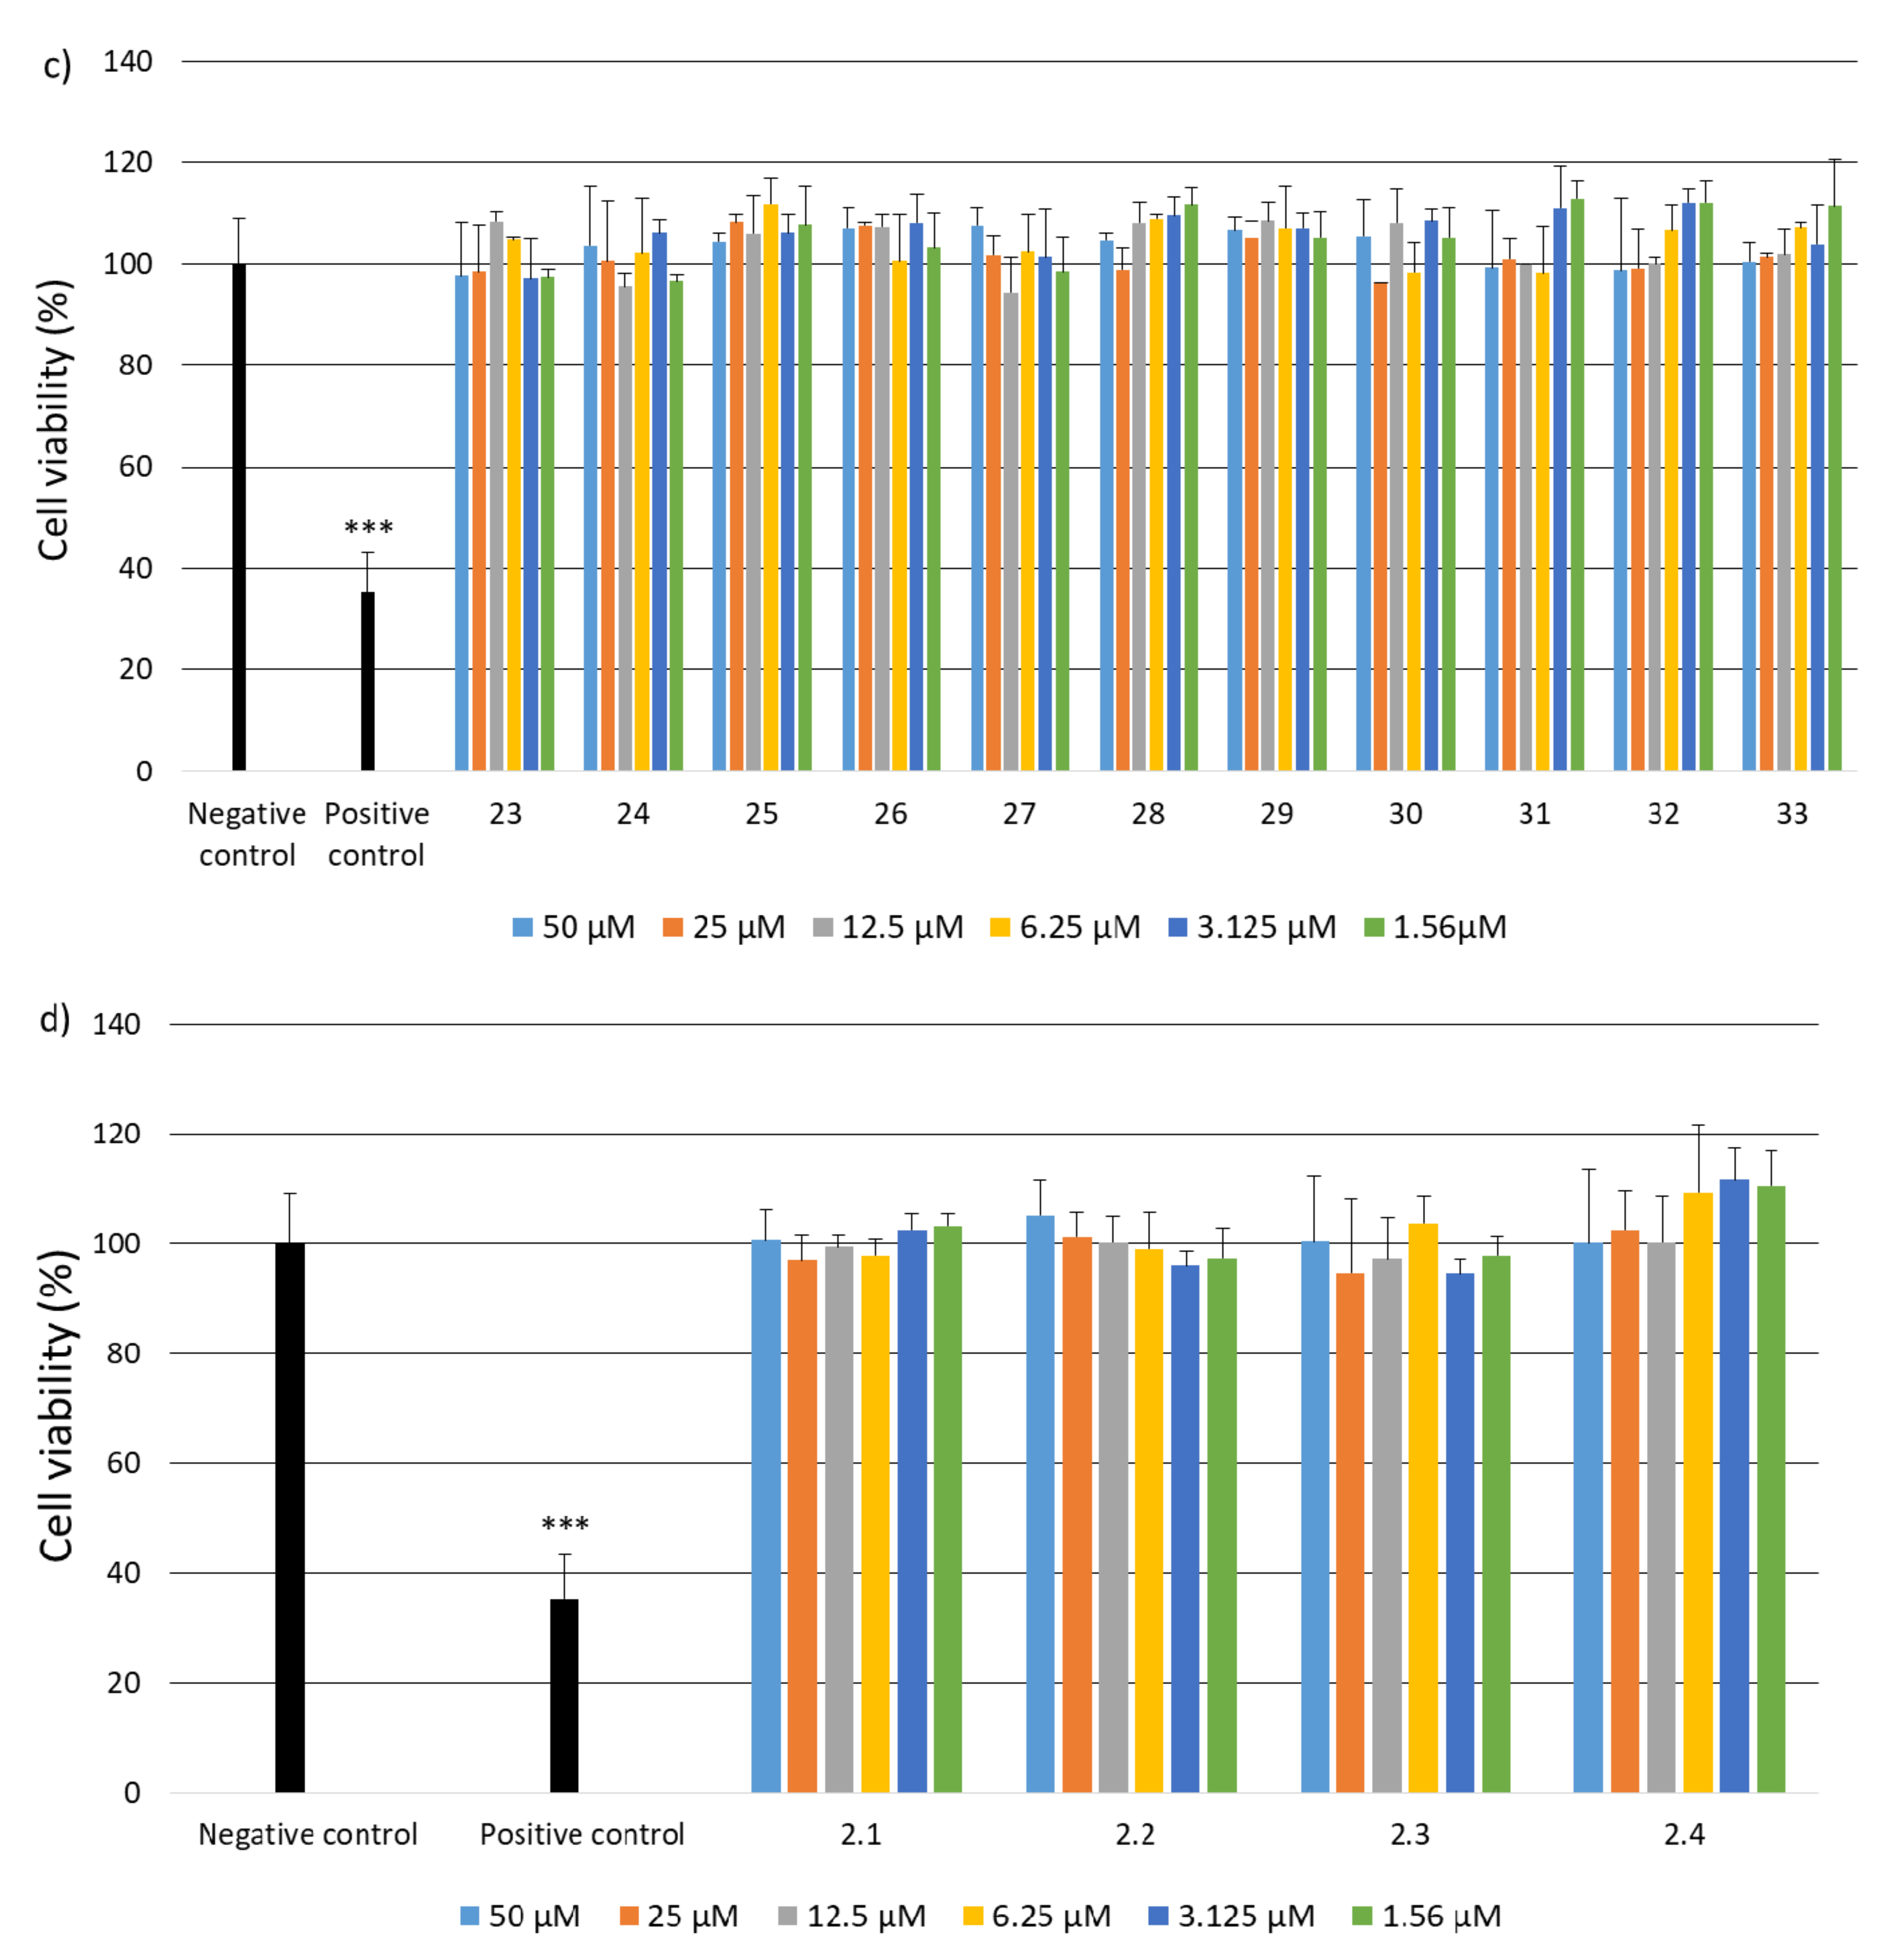

2.2. Research on Biological Activity of Collagen IV Fragments

3.7. Biological Activity Studies

- Cell Viability

- Examination of cytotoxicity of cross-linked porous materials based on the equimolar mixture of peptides 2, 4, 5, 6, 14, 15, 25, 26 and 30